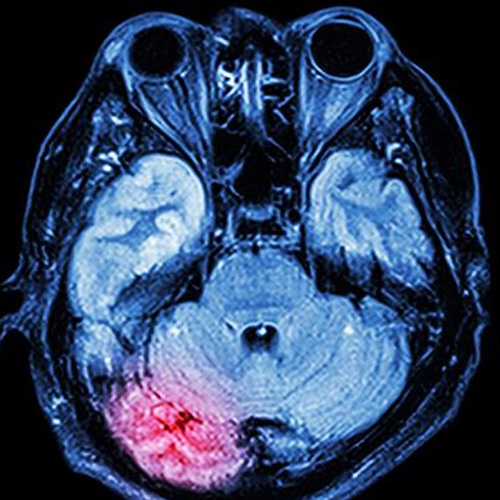

Red area shows where the brain is inflamed after concussion

The team of researchers from Adelaide, Melbourne and the United States say the brain releases a neurotransmitter called substance P in the event of a head injury, causing abnormal amounts of the tau protein to collect inside neurons.